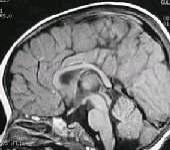

MRI (Manyetik Rezonans Görüntüleme, MRG)

Nörolojide en sık başvurulan testlerdendir. Beynin yapısı çok detaylı görüntülenir. Çok güçlü mıknatıslarla oluşturulan manyetik alandaki dokulardan alınan elektromanyetik sinyallerle görüntü oluşturulur. İyonize edici röntgen ışınları kullanılmadığından bilinen bir yan etkisi yoktur. Test sırasında hareket edilmesi görüntü kalitesini çok etkilediğinden çocuklarda yapılacak çekimler sorunlu olur ve anestezi gerekebilir.

MRI bir görüntüleme yöntemi olarak yapısal sorunların tanınmasında kesine yakın bilgi verir. Bunlar tümör, damar yumakları, felçler ve kanamalar olarak gruplanabilir. Yapısal olmayan sorunlarda ise (birçok epilepsi türü ve zihinsel aksaklıklar) MRI normaldir.